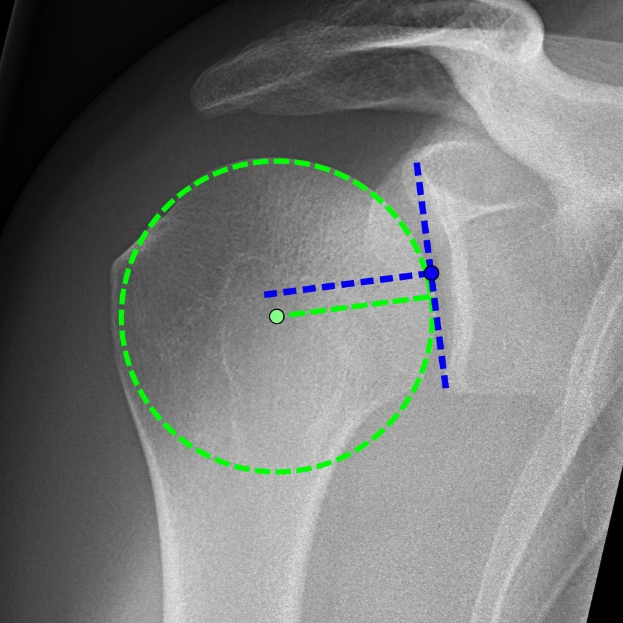

Die zweite Live-OP zeigte die Implantation einer inversen Schulterprothese. Beide Eingriffe wurden direkt aus dem OP-Saal des AKH übertragen.